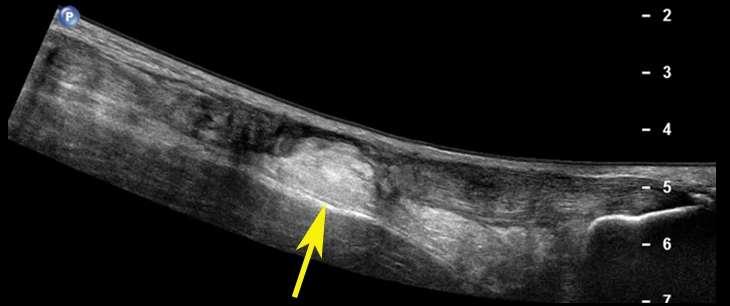

TheAchillestendon,thelargesttendon inthebody, connectsthe2majorcalfmuscles(thegastrocnemius andthesoleus)totheheelbone.Itislikelythatthe rushedreturnfromhiscalf strain meantthathetore hisAchilles,asaweakcalf canplaceexcessivestress ontheAchillestendon,whichincreasestheriskofan Achillestearorrupture.

This injury wascontroversialassomethink that hewas misdiagnosed in the first place. Dr. David Chao, an orthopaedic surgeon and Team Physician for an NFL team, wrote in the San Diego tribune that Durant’s expression when he sustained the initial injury on May 8th indicatedapossibleAchillestendonrupture,instead of it just being a calf injury. He said that the team specifically avoided the term “calf muscle” and opted for the more ambiguous and broad term “calf,” as an attempt to cover up a more serious injury, so that fans wouldn’t be concerned for his health during the Finals run.

AnultrasoundimageofanAchillestear(notKD’sone)is shownbelow.

Credit:InternationalDayofRadiology

The potential misdiagnoses, along with his rushed return, were perhaps important factors leading to KD’s season ending injury. If KD continued to be sidelined, perhaps he would not have su ered the Achilles rupture.